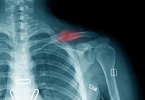

骨质退行性变,通常指的是关节骨质发生退变或者老化,可能是由于肥胖、劳损、关节畸形等原因导致的,而且随着年龄的逐渐增长,也可出现生理性改变,由于机体的生长机能减退,其代谢功能也会逐渐减退,从而引起一系列症状,比如疼痛、弯腰困难、活动受限、肢体麻木等症状,通过积极的治疗,可延缓病情进一步发展,多无法达到治愈的目的。